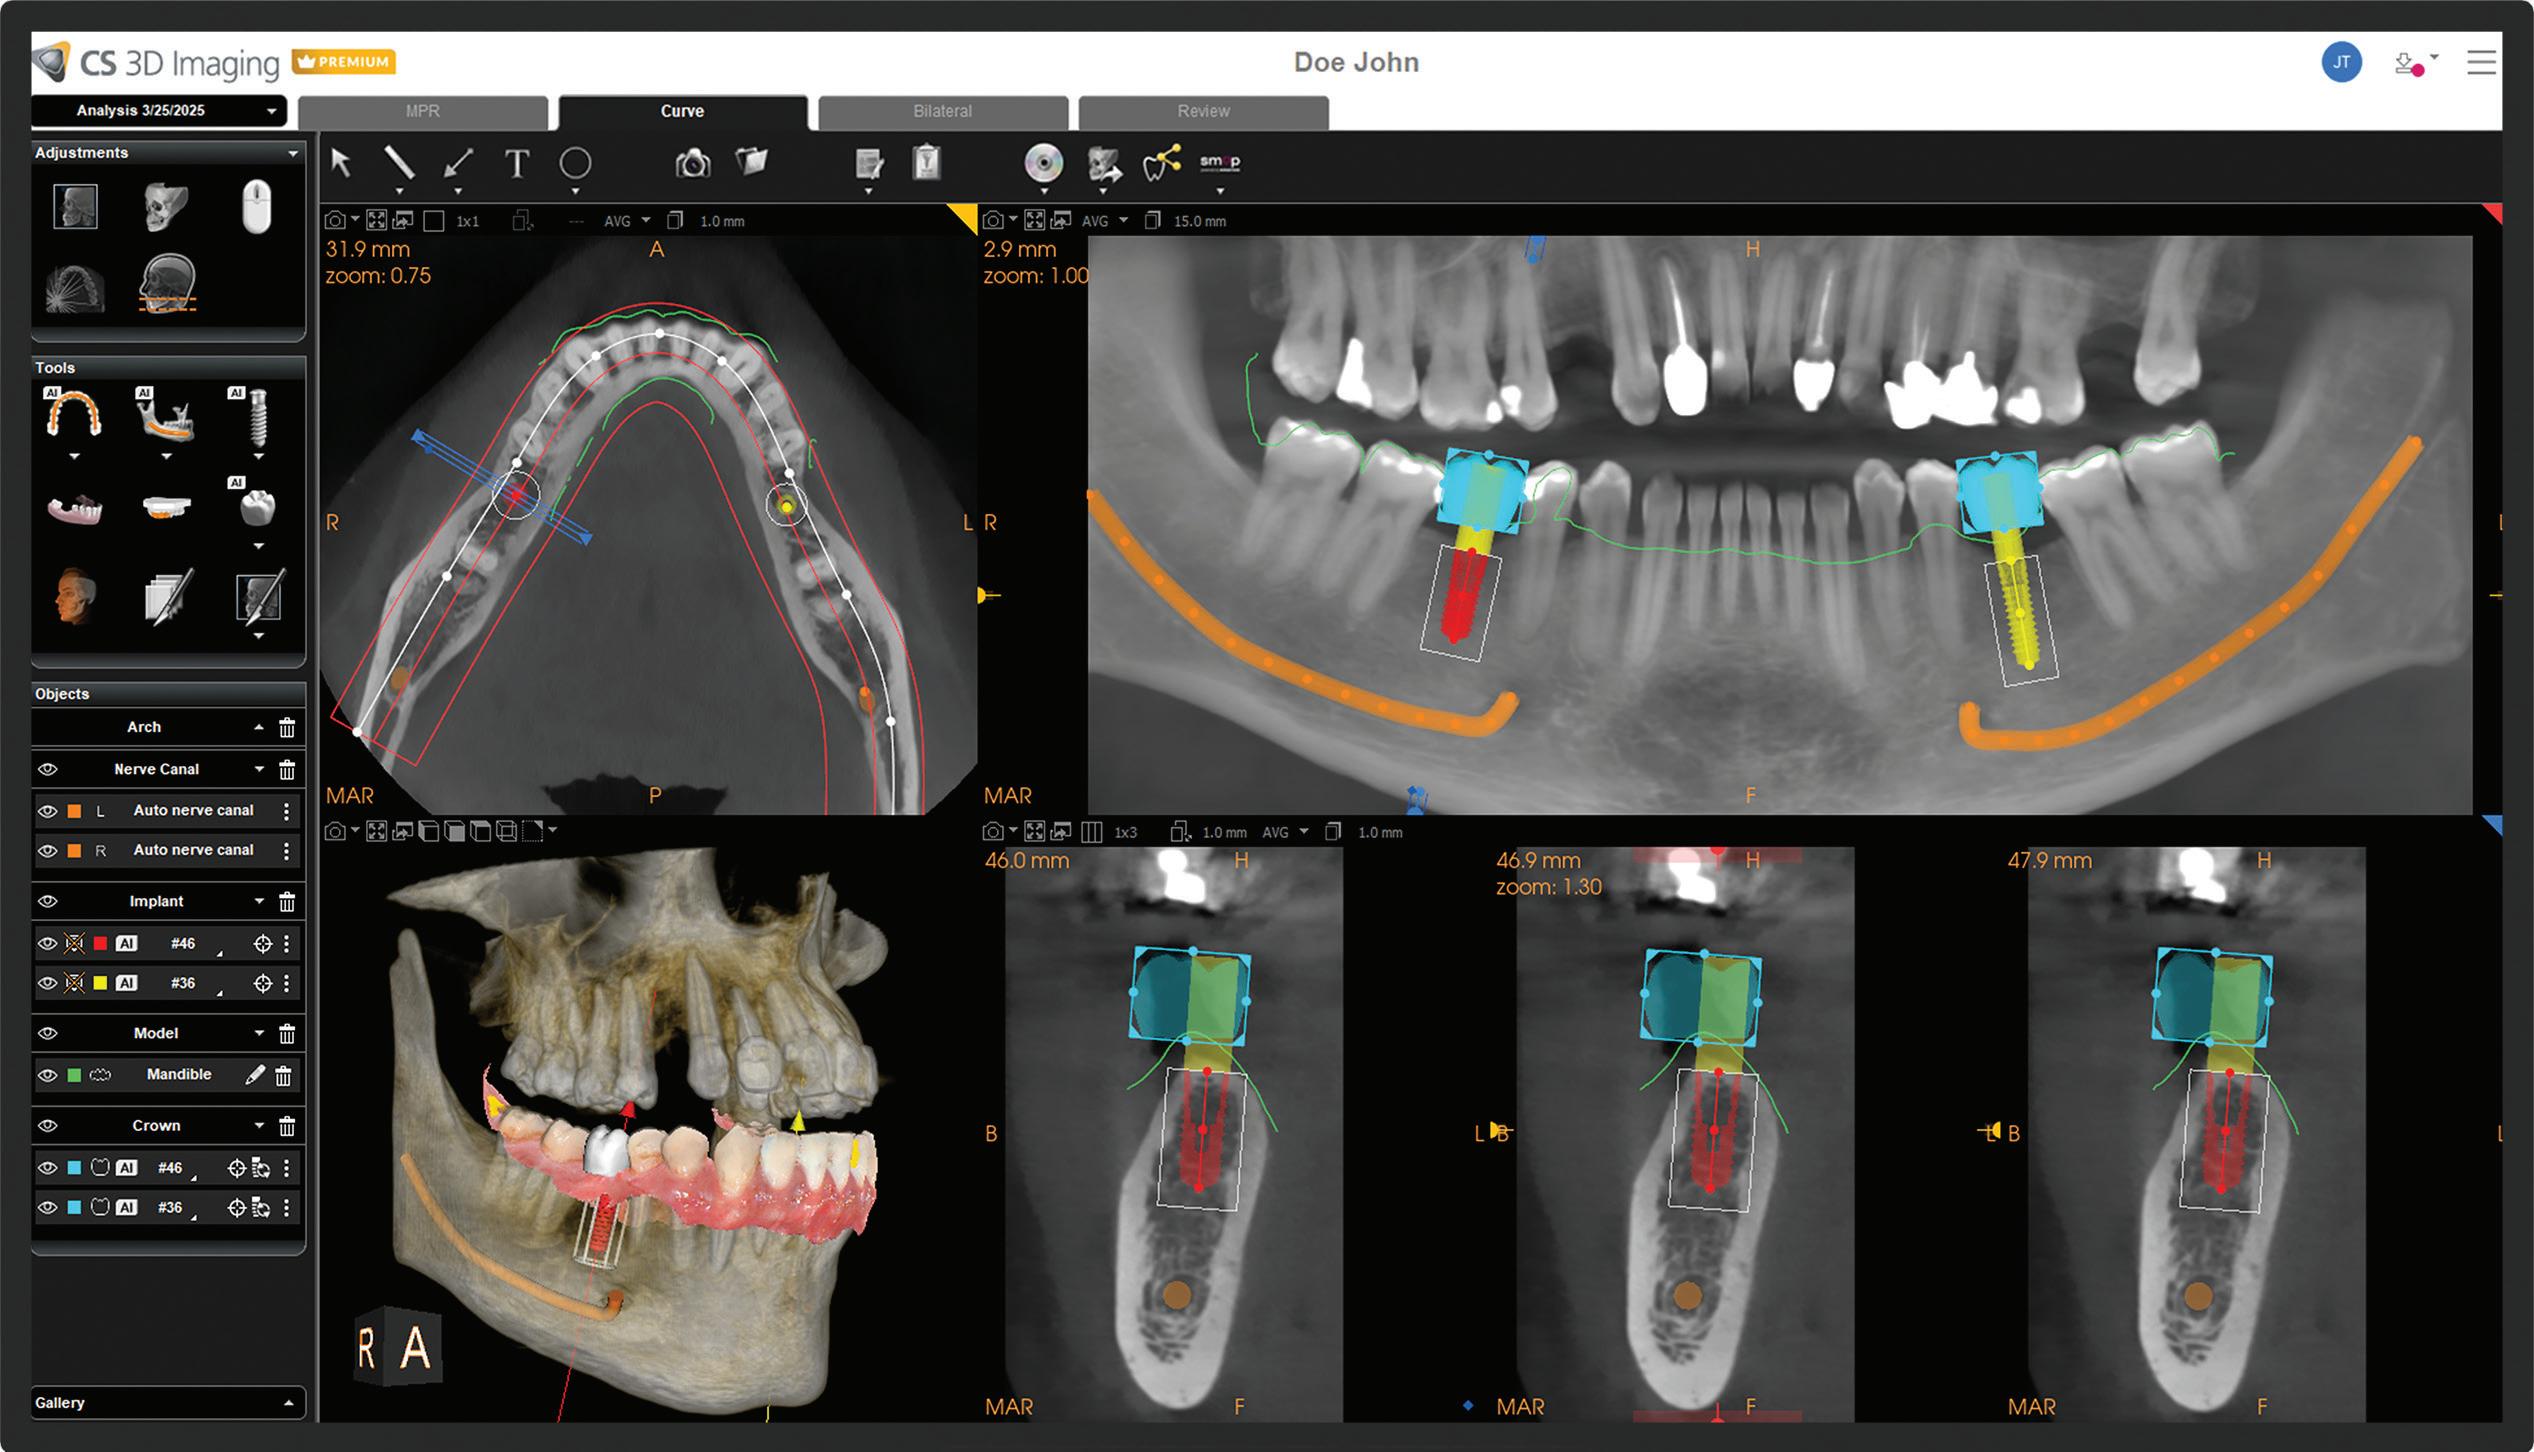

In its continuing commitment to reimagine and improve solutions for the dental industry, Carestream Dental has launched the Advance Edition of the CS 8200 3D, along with the latest updates in automated implant planning. The CS 8200 3D Advance Edition is the newest addition to the CS 8200 3D Family and builds on the success of its award-winning predecessors with extended fields of view—including two new larger FOVs—and AI-powered software that streamlines and automates the implant planning workflow.*

• AI-powered implant planning:* The enhanced implant planning module automates the implant workflow, allowing practitioners to plan implants faster and with greater precision.

Additionally, new AI-assisted software accelerates the entire implant planning process by automating time-consuming tasks. Now, preparing data for implant cases— like merging CBCT volumes with digital impressions—designing virtual crowns and digitally placing implants is all handled automatically, making implant planning faster and easier. When combined with a prosthetic-driven approach, these software updates improve treatment predictability and give doctors the confidence to deliver precise and successful implant outcomes.